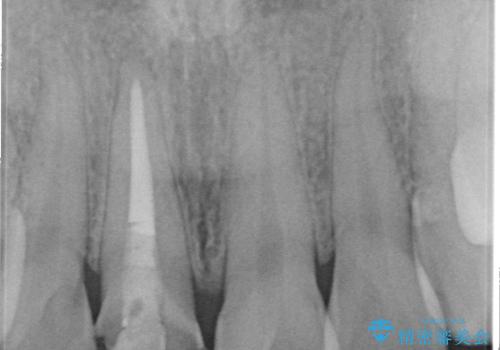

根管治療について

保険根管治療は回数がかかることが多く、終了予定がわかりにくいです。

当院では、根管治療は長い時間のご予約を頂き、多くの場合2~3回で終わります。

根管治療は歯内の治療なので患者様には見えない場所ですが、ここが細菌で汚染されると激しい痛みや長引く違和感の原因になります。

当院では、清潔な治療を徹底し、顕微鏡を使用した精密な治療を行っています。

症状や根管の状態により、治療金額が異なります(5~10万円目安)。治療回数による費用負担の増減はありません。